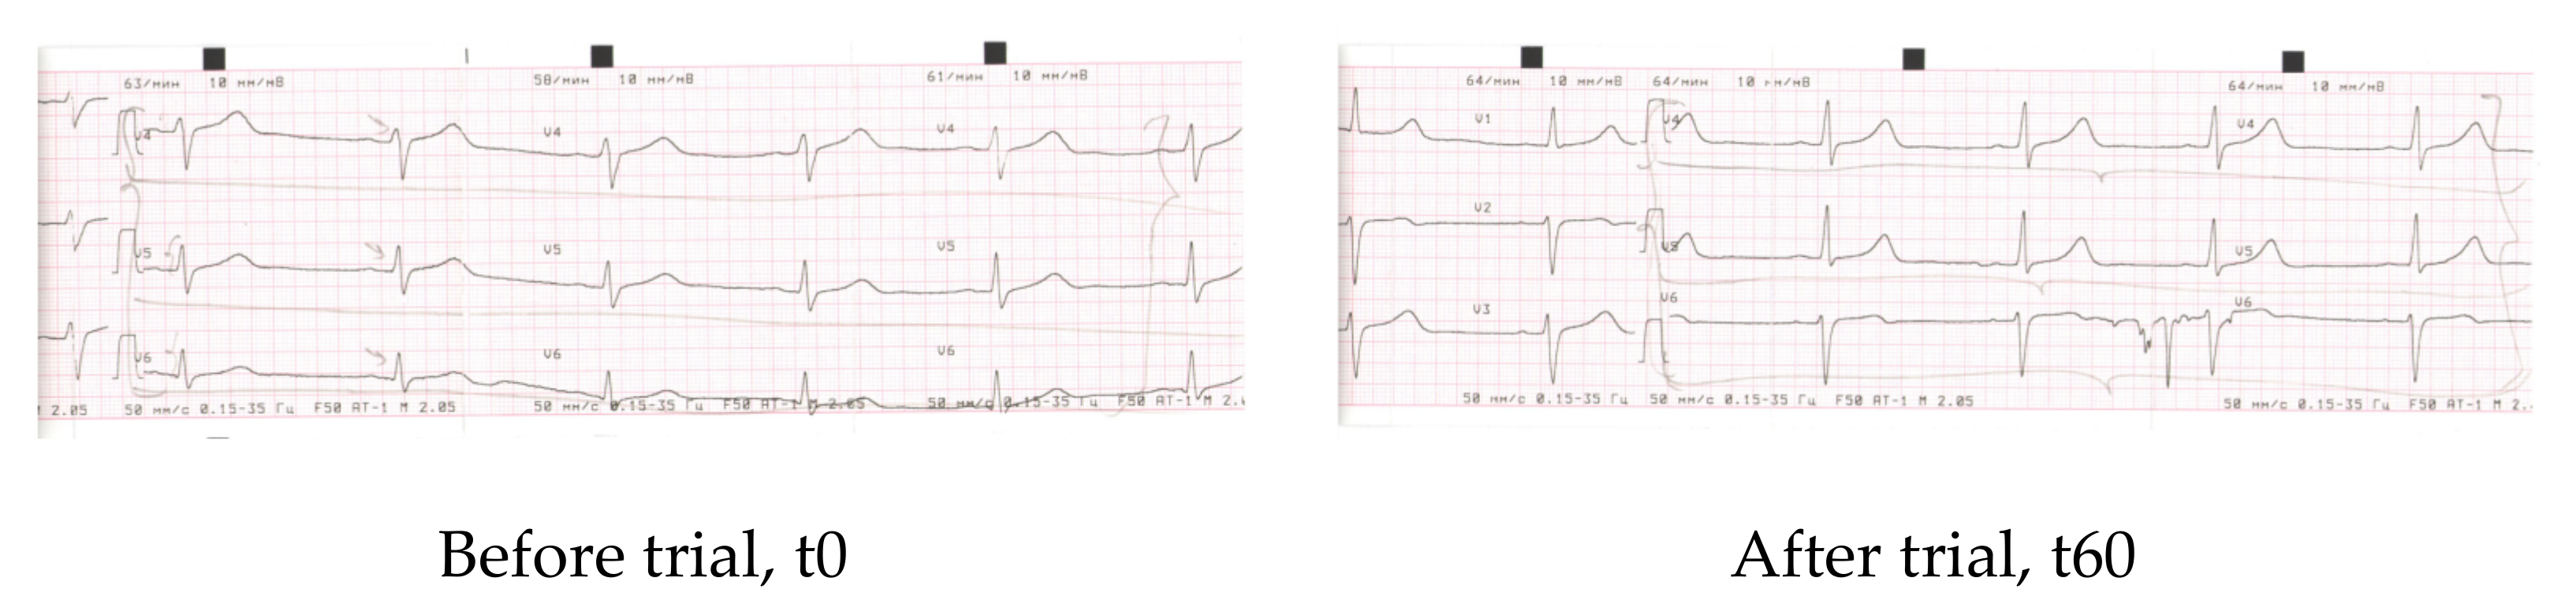

Electrocardiography measurements were carried out in the beginning (t0) and after the cessation of the trial (t60). The results were analysed by a cardiologist, and their physiological/pathological meanings were described in detail.

Electrocardiography was recorded and described by an experienced doctor-cardiologist in the beginning and at the cessation of the clinical study (scans of electrocardiography records are collected in the Appendix C. (Scan A1, Scan A2, Scan A3, and Scan A4). The doctor found that, before entering the trial, a major part of the volunteers (n = 41) did not show any abnormalities in the cardiography parameters. However, four people from the CTR group and five people from the EXP group exhibited initial stages of metabolic abnormalities in cardiac muscles, as revealed by characteristic changes in the electrocardiography peaks (V4–V6). When analysed for the second time, none of the volunteers of the EXP group showed negative metabolic changes of electrocardiography curves (Appendix C. ScansA1–A3). At the same time, all four participants of the CTR group with metabolic abnormalities retained the same after the trial (Appendix C. Scan A4).

Obviously, the human cohort was too small to come to definite conclusions that HIDW consumption for at least 2 months could alleviate potentially dangerous baseline metabolic alterations in the myocardium. However, keeping in mind that the improvement of cardiac metabolism corresponded to improved heart functions, HIDW consumption under the conditions of this study could result in a markedly faster recovery and in a better physiological state after moderate physical load (Table 5 and Table 6).

The improvement of cardiovascular system metabolism and function upon consumption of HIDW by animals has been previously shown [34]. This corresponds to our observations in the human cohort (Appendix C) and could be at least partly explained by the increase in ATP levels available for cardiac muscle contraction-relaxation, by an improvement of energy-producing metabolism and by a water loss through enhanced urination or sweating. Of course, these limited data of electrocardiography should be considered as preliminary observations. Larger studies may confirm or reject them; therefore, they are not included in the study conclusions.

Appendix C

Electrocardiography scans and their description.

Scan 3. EXP group, patient M., M, 33 y.

| Parameter | Before | After 60 days |

| Rhyme | Sinus | Sinus |

| Heart rate | 74 | 67 |

| PQ | 0.18″ | 0.16″ |

| QRS | 0.08″ | 0.08″ |

| QT | 0.40″ | 0.38″ |

| QRS axis | Horizontal +38 | Horizontal +38 |

| Conclusions | Dysmetabolic alterations of myocardium (frontal and lateral walls of the left ventricle) (V4-V5) | Improvement of re-polarisation of (V4–V5), increment of peaks V4–V5 |

Scan 4. CTR group, patient M., F, 44 y.

| Rhyme | Synus | Synus |

| Heart rate | 68 | 70 |

| PQ | 0.12″ | 0.14″ |

| QT | 0.38″ | 0.38″ |

| QRS axis | Vertical +77 | Vertical +77 |

| Conclusions | Dysmetabolic alterations of myocardium (frontal and lateral walls of the left ventricle) (V4–V6) | Dysmetabolic alterations of myocardium (frontal and lateral walls of the left ventricle) (V4–V6) |